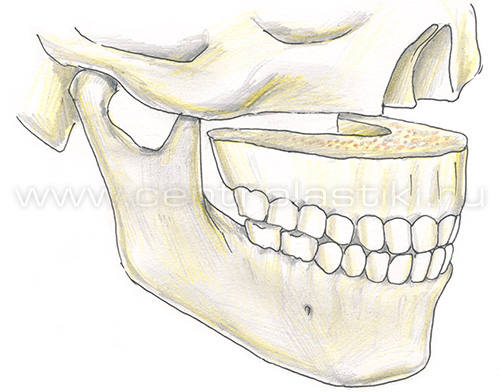

Остеотомия верхней челюстиПоказания Коррекция аномалий развития верхней челюсти (микрогнатия, ретрогнатия верхней челюсти). Остеотомию на верхней челюсти проводят как этап ортодонтического лечения. Операция Остеотомия верхней челюсти выполняется внутриротовым доступом под эндотрахеальным наркозом, выполняется разрез слизистой оболочки полости рта и надкостницы, разрез производят несколько выше переходной складки верхней челюсти от 7 до 7 зубов. Края раны раздвигаются, тем самым осуществляется доступ к передней стенке верхней челюсти.  На передних и боковых стенках верхней челюсти слева и справа производятся разметки линий распилов.  Специальными пилками проводится остеотомия по разметкам.  Затем отделяется распиленный фрагмент и перемещается в заранее выбранное положение.   Фиксация перемещенного фрагмента в новом положении осуществляется титановыми мини-пластинками.  Длительность Операция занимает от 1,5 до 3 часов и проводится под наркозом. В течение 1 месяца после лечения сохраняется отечность мягких тканей лица, может отмечаться нарушение чувствительности верхней губы и щек, чувствительность восстанавливается самопроизвольно через некоторое время. В ряде случаев после операции для обеспечения хорошего срастания костей проводят межчелюстное шинирование , верхняя и нижняя челюсти фиксируются друг к другу специальными приспособлениями, так что полное открытие рта невозможно. В этот период (2-3 недели) возможно питание только протертой и жидкой пищей. После операции остеотомии верхней челюстиВ послеоперационном периоде возможно ношение ортодонтической брекет системы для правильного смыкания зубных рядов верхней и нижней челюстей. Реабилитационный период В течение 1-3 суток после операции рекомендовано нахождение в стационаре под наблюдением медицинского персонала (длительность нахождения в стационаре может быть продлена до 10 суток в зависимости от течения послеоперационного периода). Длительность реабилитационного периода зависит от восстановительных способностей организма. Эффективность Окончательный результат операции можно наблюдать через 3-6 месяцев. В послеоперационном периоде могут сохраняться отеки в течение 2-4 недель, в зависимости от индивидуальных особенностей восстановление протекает с разной скоростью. |